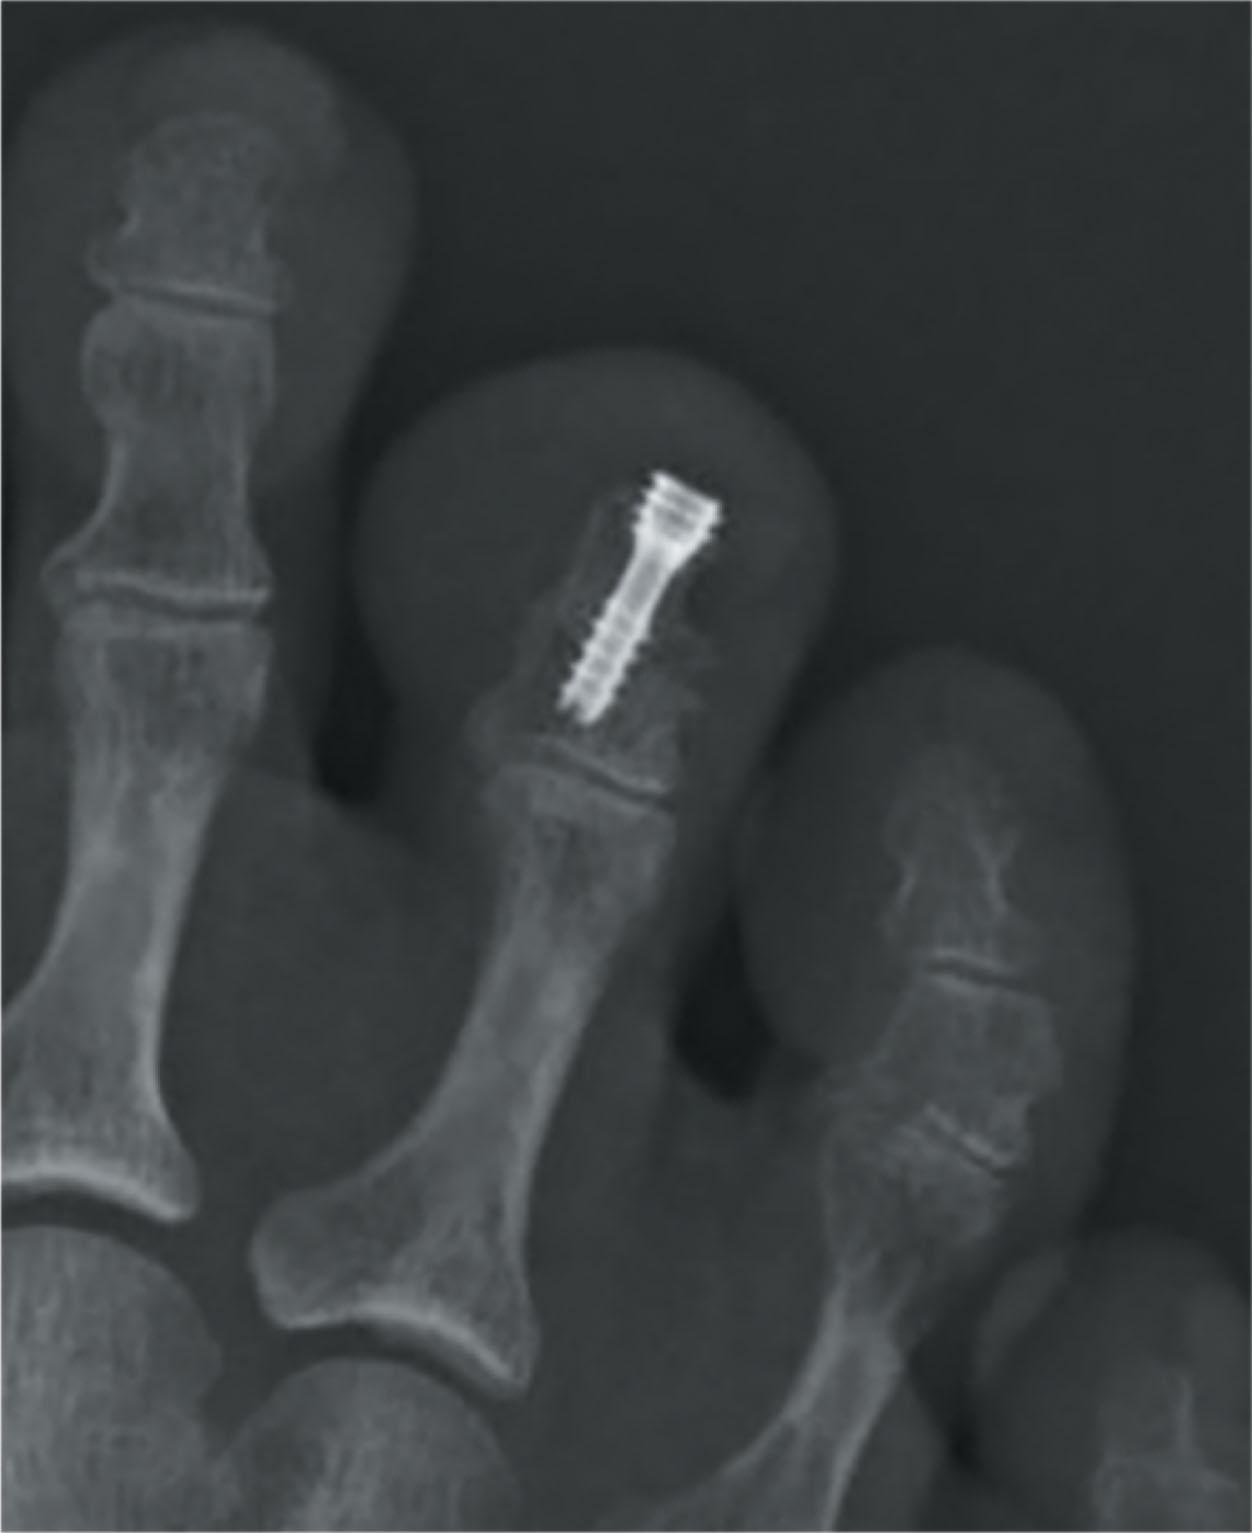

Intramedullary fixation for hammer toe correction has been advocated in an effort to secure permanent fixation without the use of Kirschner wires. Absorbable implants, screw fixation ( Figs. 9-41 and 9-42 ), wire loops, and other permanent intramedullary devices ( Fig. 9-43 ) have all been reported.

Attempts at more permanent fixation have been reported. Lane, Caterini et al, and Vitek have reported the use of either a distally introduced intramedullary screw or an oblique screw fixation (see Figs. 9-41–9-43 ). Vitek reported a 93% fusion rate. Caternini et al reported a similar fusion rate; however, this technique sacrifices the DIP joint with fixation that crosses both interphalangeal joints. Konkel et al reported the use of an absorbable intramedullary pin for fixation of a hammer toe repair. A 73% union rate was noted. Three mallet toes and eight transverse plane deformities were reported, as well as a similar rate of “floating toes.”

The results of DIP joint sacrificing fixation has led to the development of DIP joint sparing intramedullary fixation. While this list is not exhaustive, it includes: the Smart Toe II (Stryker, Kalamazoo, MI), the DynaNite (Arthrex, Naples, Flor.), the Toe grip (Synchro Medical, Lyon, France), the Stayfuse (Tornier, Minneapolis, Minn.), the Ipp-On (Integra, Plainsboro, NJ), the Pro-Toe (Wright Medical, Memphis, Tenn.), the TenFuse (Wright Medical, Memphis, Tenn.), the Hat-trick (Smith and Nephew, Andover, Mass.), the Hammerfix (Extremity Medical, Parsippany, NJ), the Nextra (Zimmer Biomet, Warsaw, Ind.), and the CannuLink (Wright Medical, Memphis, Tenn.). Bioabsorbable fixation with either a PDS pin, polyketone, or PLLA screw has also been described.

Several of the available implants have published results. While there are no randomized controlled trials, Wei et al published a systematic review of previously published studies on intramedullary implants that included a control group with Kirchner wires. They demonstrated similar clinical outcomes with respect to pain levels, patient satisfaction, foot-related function, and surgical complication rates. Ellington et al reported a 60% union rate in 38 toes and sagittal or coronal plane malalignment in 18% of cases ( Fig. 9-46 ). Only three patients had revision surgery; the authors felt the implant assisted in maintaining alignment despite a union rate very similar to Kirschner wire fixation. Roukis reported his results with the Smart Toe in 30 toes. The fusion rate was 93%; malunion occurred in 7%. Avenrous published a report of 142 patients with 1-year follow-up of the Toegrip and reported a 94% satisfaction rate with a PIP joint arthrodesis rate of 84%. Catena et al reported a 100% satisfaction rate, an 81% bony union rate in a case series of 42 Smart Toes at 1 year follow-up. Obrador compared standard K wire fixation with the Smart Toe implant as well as the TenFuse implant and demonstrated slightly higher patient satisfaction with intramedullary fixation but similar outcomes. Scholl compared the smart Toe to a buried Kirchner wire and noted that despite similar clinical outcomes, only 68.9% of the Smart Toe implants achieved an arthrodesis across the PIP joint, which was consistent with their results in the Kirchner wire group.